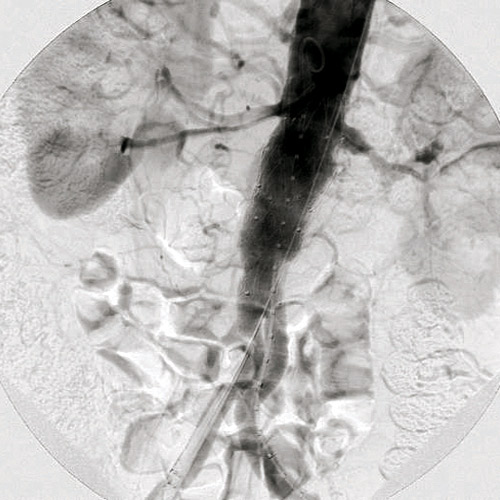

نجح فريق الأشعة التداخلية بالتعاون مع قسم جراحة الأوعية الدموية في إجراء عملية لإصلاح الشريان الأورطي عن طريق تركيب دعامات بواسطة القسطرة التداخلية «إيفار» عن طريق فتحة صغيرة في الجلد. ويعتمد الأسلوب الجديد على تصليح التمدد بالشريان الأورطي عن طريق تركيب دعامة صناعية من خلال قسطرة يتم إدخالها من شرياني الفخذين مما يعجل بالشفاء وتقليل المضاعفات الجراحية والنزيف ومدة البقاء تحت الرعاية المركزة خاصة لبعض الحالات التي لاتسمح حالتهم البدنية والصحية بالتخدير فضلا عن اختصار زمن وتكلفة العلاج مقارنة بالعمليات الجراحية التقليدية. حيث كان يتم في السابق أجراؤها عن طريق الشق الجراحي وما يعقبه من آلام شديدة للمريض ومضاعفات جانبية وطول فترة البقاء في المستشفى.